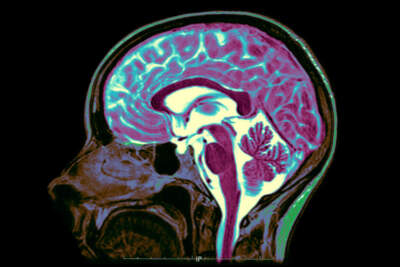

Brainwaves: Why is the brain such a mystery?

The brain is the organ that makes us who we are. It’s our conduit between reality and thought. But somehow, we’ve only scratched the surface in understanding how the brain...